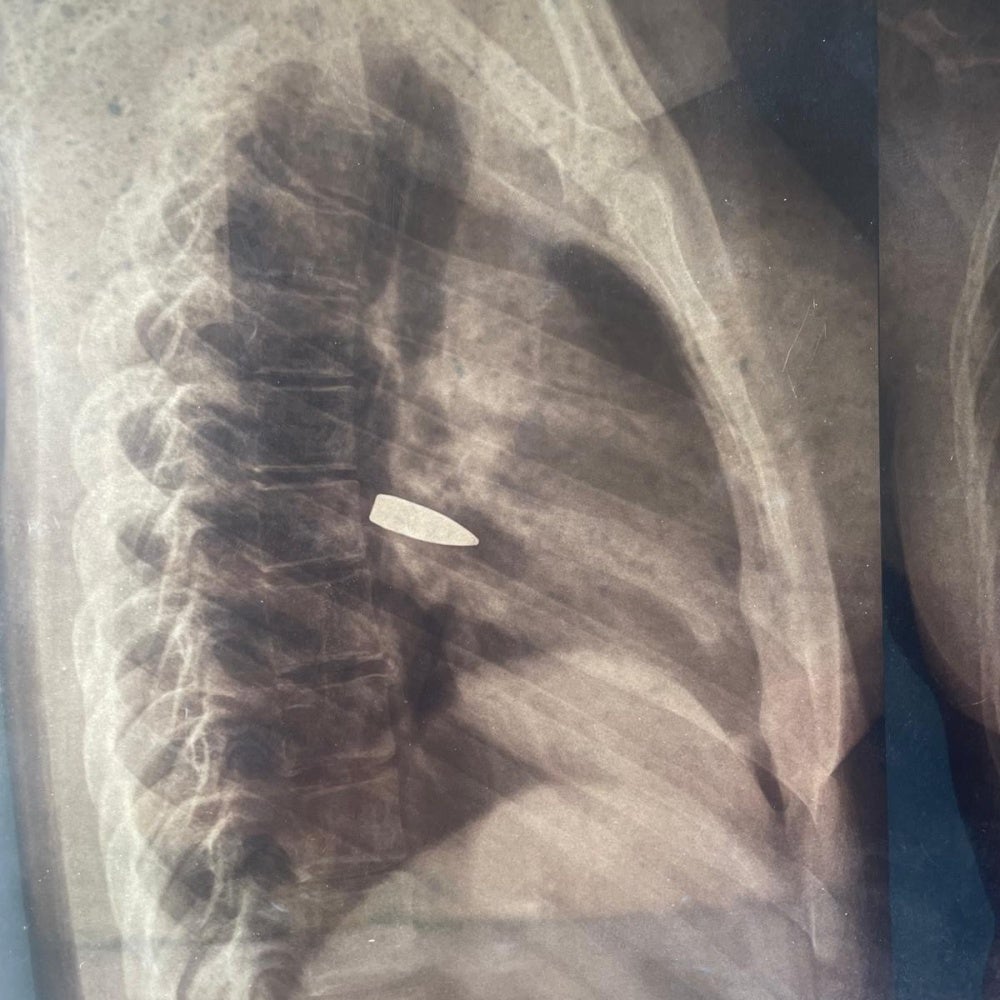

The organizations saw x-rays from six people who had bullets lodged in their bodies. Three of the people had not yet had the bullets removed at the time of interview in August.

When we saw the blood we took him to the hospital, it was around 10:45 p.m. when we arrived. They made us pay 7,000 CFA (about $12) for the x-ray and told us to go home. We had to go back to the hospital four times and had to pay each time. The family is in shock that this could happen. We were scared that he would die … The child won’t sleep in the same room where he was shot. He is traumatized.